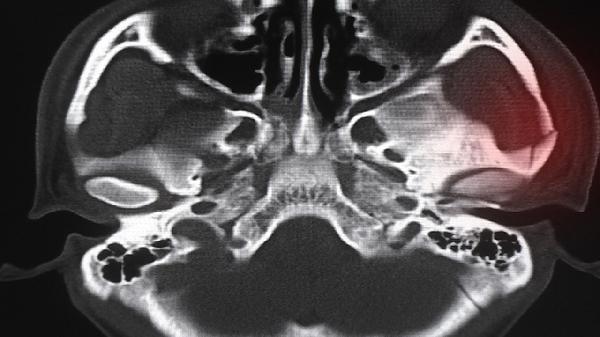

手腕部X光片能直观显示骨骺线状态,未闭合者可见清晰透亮生长板,闭合后则消失。骨龄与实际年龄差值超过±2岁具有临床意义,骨龄超前提示闭合风险。医院常用Greulich-Pyle图谱法或TW3计分法评估,检查时需屏蔽性腺等敏感部位。

膝关节或踝关节MRI能三维观察生长板厚度,分辨率达0.2mm,适合微闭合状态判断。超声检查虽无辐射但准确性较低,适用于儿童筛查。数字化X线骨密度仪可同步评估骨质成熟度,价格约为200-500元/次。